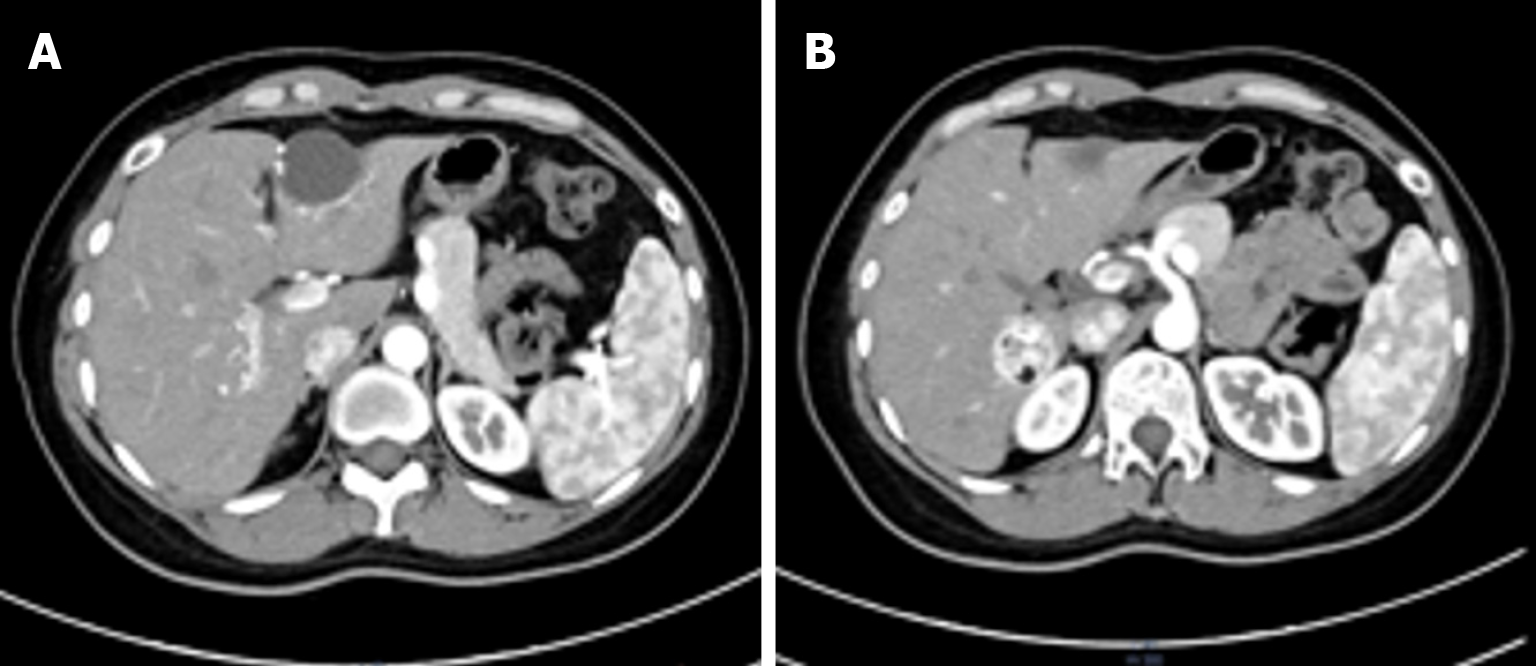

The patient’s postoperative recovery was uneventful, with all routine laboratory parameters remaining within normal limits. Follow-up assessments indicated that the patient was asymptomatic and maintained good overall health. Contrast-enhanced CT performed 3 months postoperatively demonstrated partial resection of the left hepatic lobe, with a localized cystic hypodense area at the site of resection. The right hepatic lesion treated with TAE had decreased in size from 33 mm to 27 mm. No radiological signs of recurrence nor other abnormalities were detected (Figure 5).